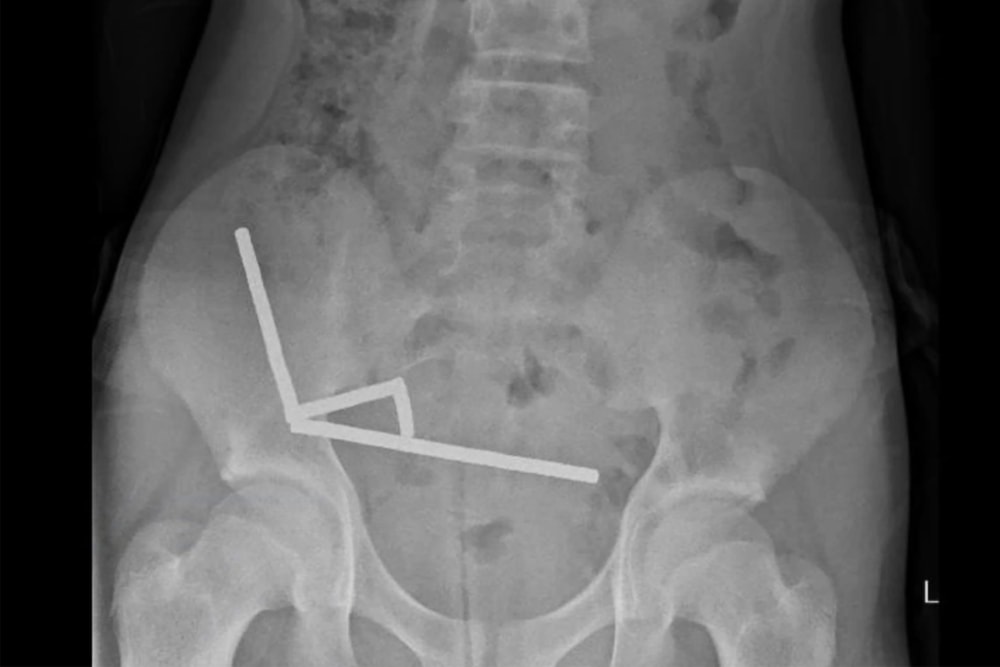

新西兰北岛一所医院的医生近日为一名 13 岁男孩实施紧急手术,从他体内取出多达 100 颗强力磁铁。这些磁铁在男孩肠道中相互吸附形成四条链状结构,导致严重损伤。医生不得不为他切除部分肠段。

据悉该男孩从网上购买并吞下了大约 80 到 100 颗 5×2 毫米大小的高功率钕磁铁。在经历四天腹痛后,他被送入 Tauranga 医院。根据该医院医生周五(10 月 24 日)发表在《新西兰医学杂志》上的报告,外科医生成功取出了这些磁铁,男孩在医院住了八天后成功出院。